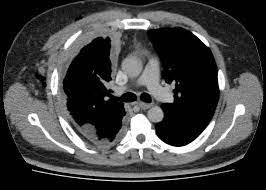

Uso de inhibidores del SGLT2 o de la DPP-4 como terapia complementaria y riesgo de eventos quirúrgicos por enfermedad arterial periférica

04 diciembre 2024

En este estudio de cohorte retrospectivo se compara el riesgo de un resultado compuesto de cirugía por enfermedad arterial periférica (EAP), incluidos los procedimientos de revascularización periférica y amputación, entre los nuevos usuarios de inhibidores del cotransportador de sodio-glucosa 2 (SGLT2i) y los de inhibidores de la dipeptidil peptidasa 4 (DPP-4i), observando mayor incidencia con los SGLT2i (HRa 1,18 [IC95 %: 1,08-1,29]). Diabetes Care, 2 de diciembre de 2024.